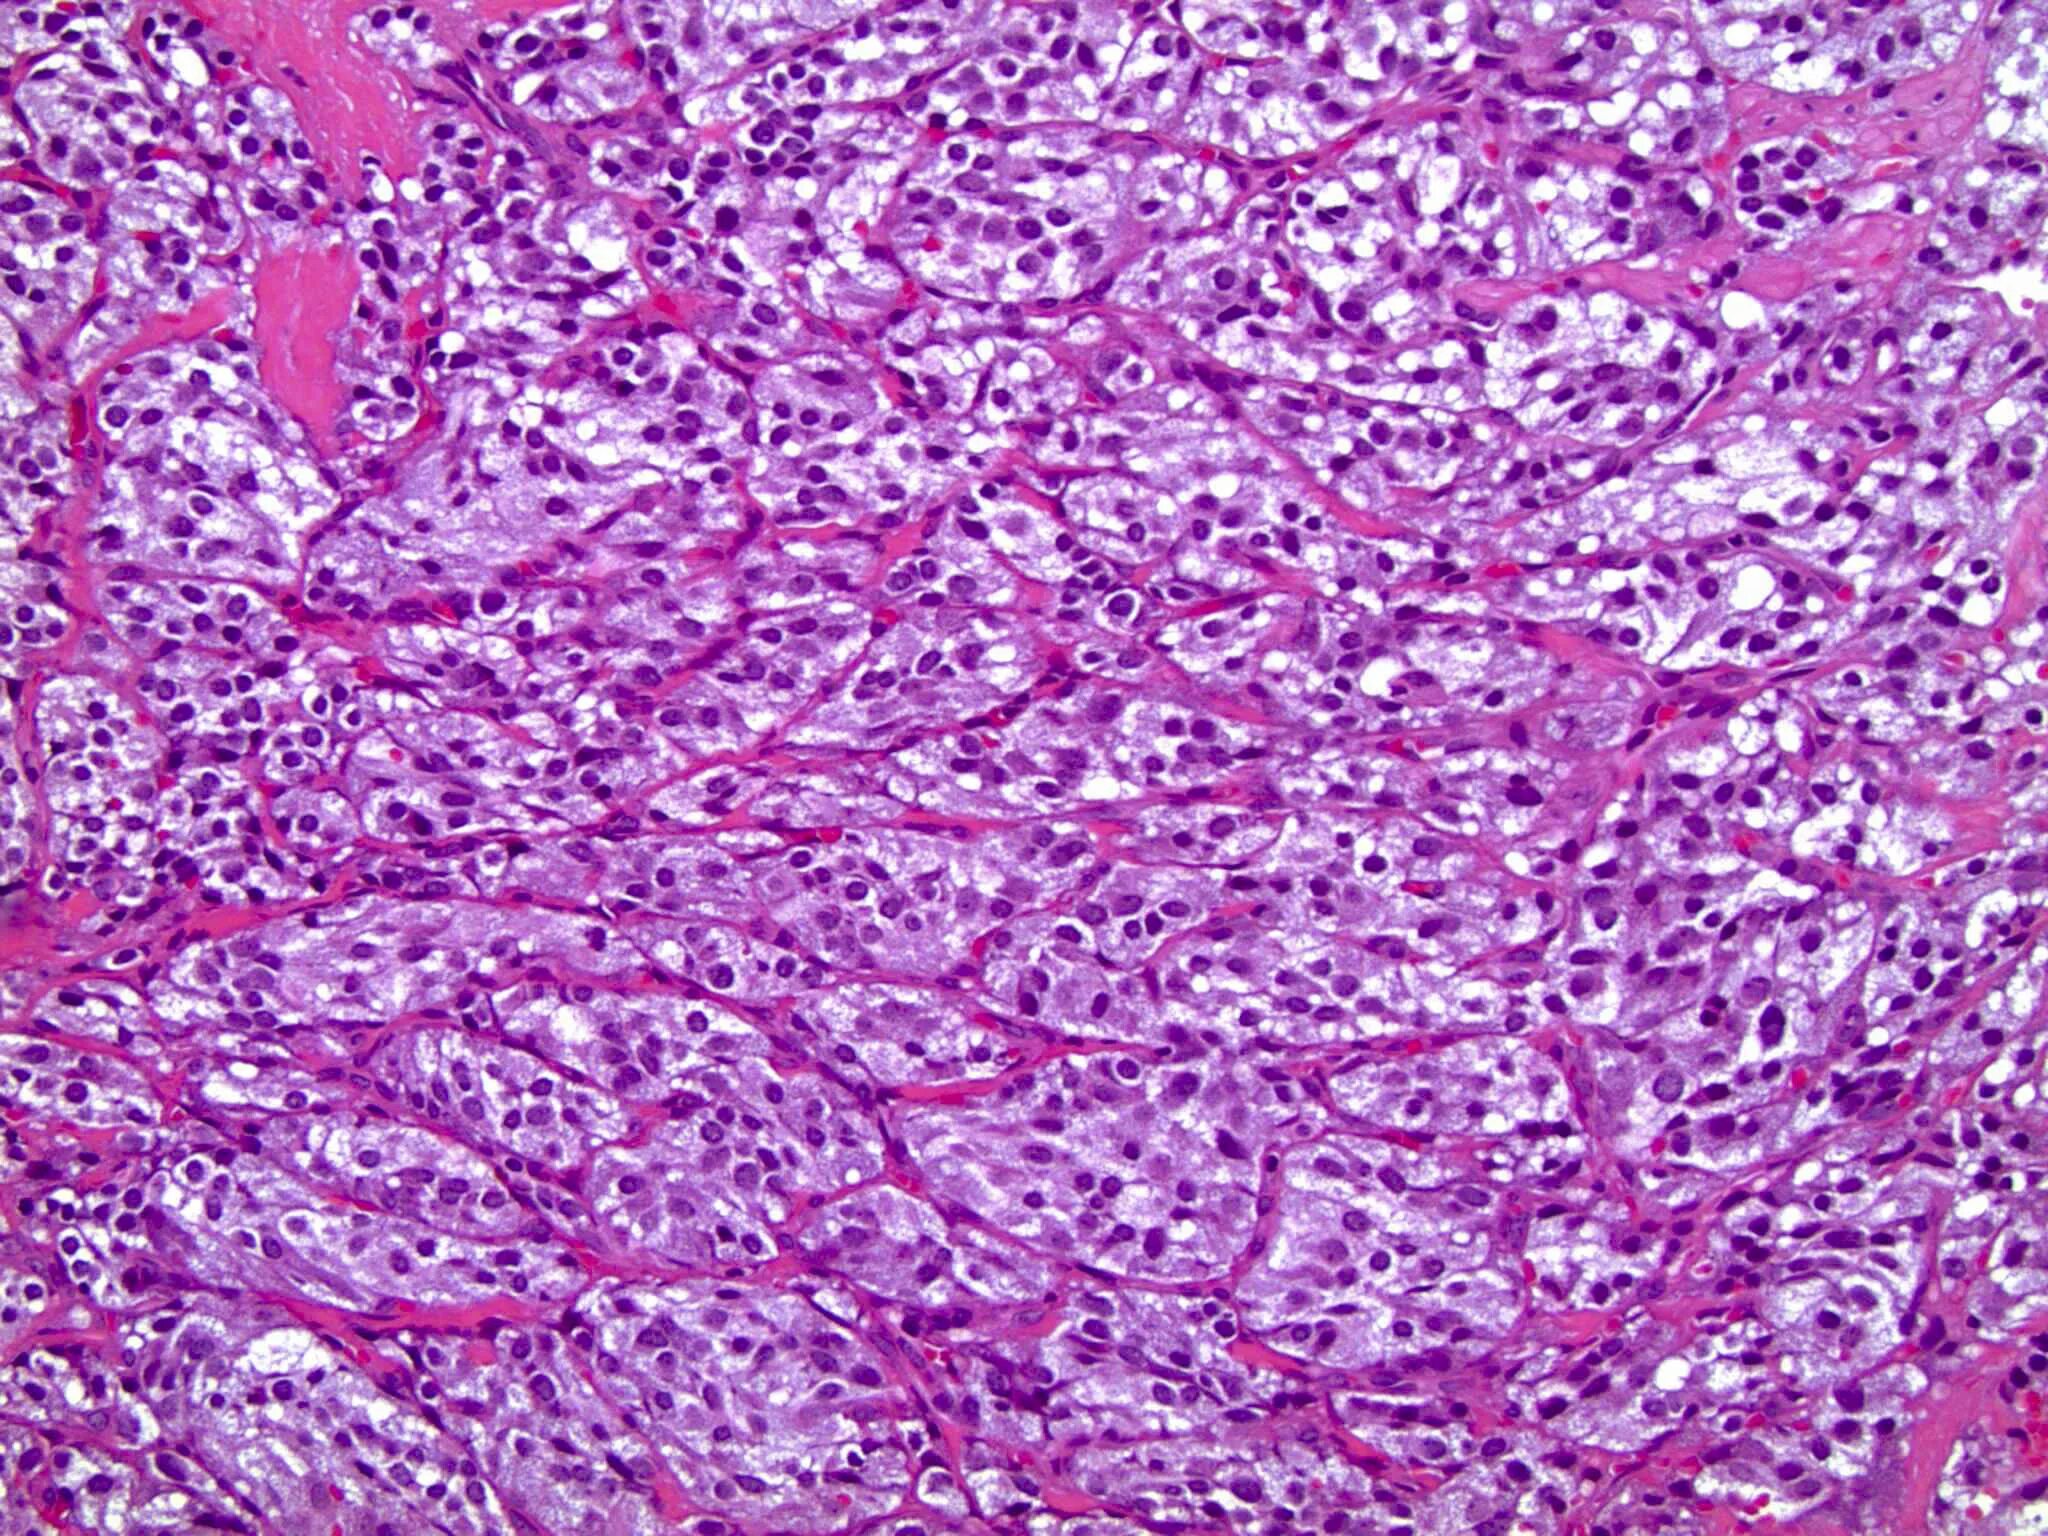

Пограничная гистология